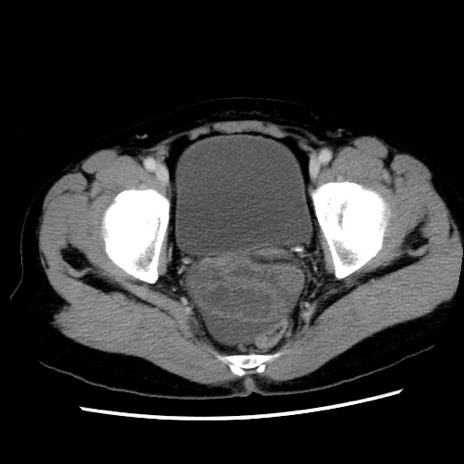

矢状断像